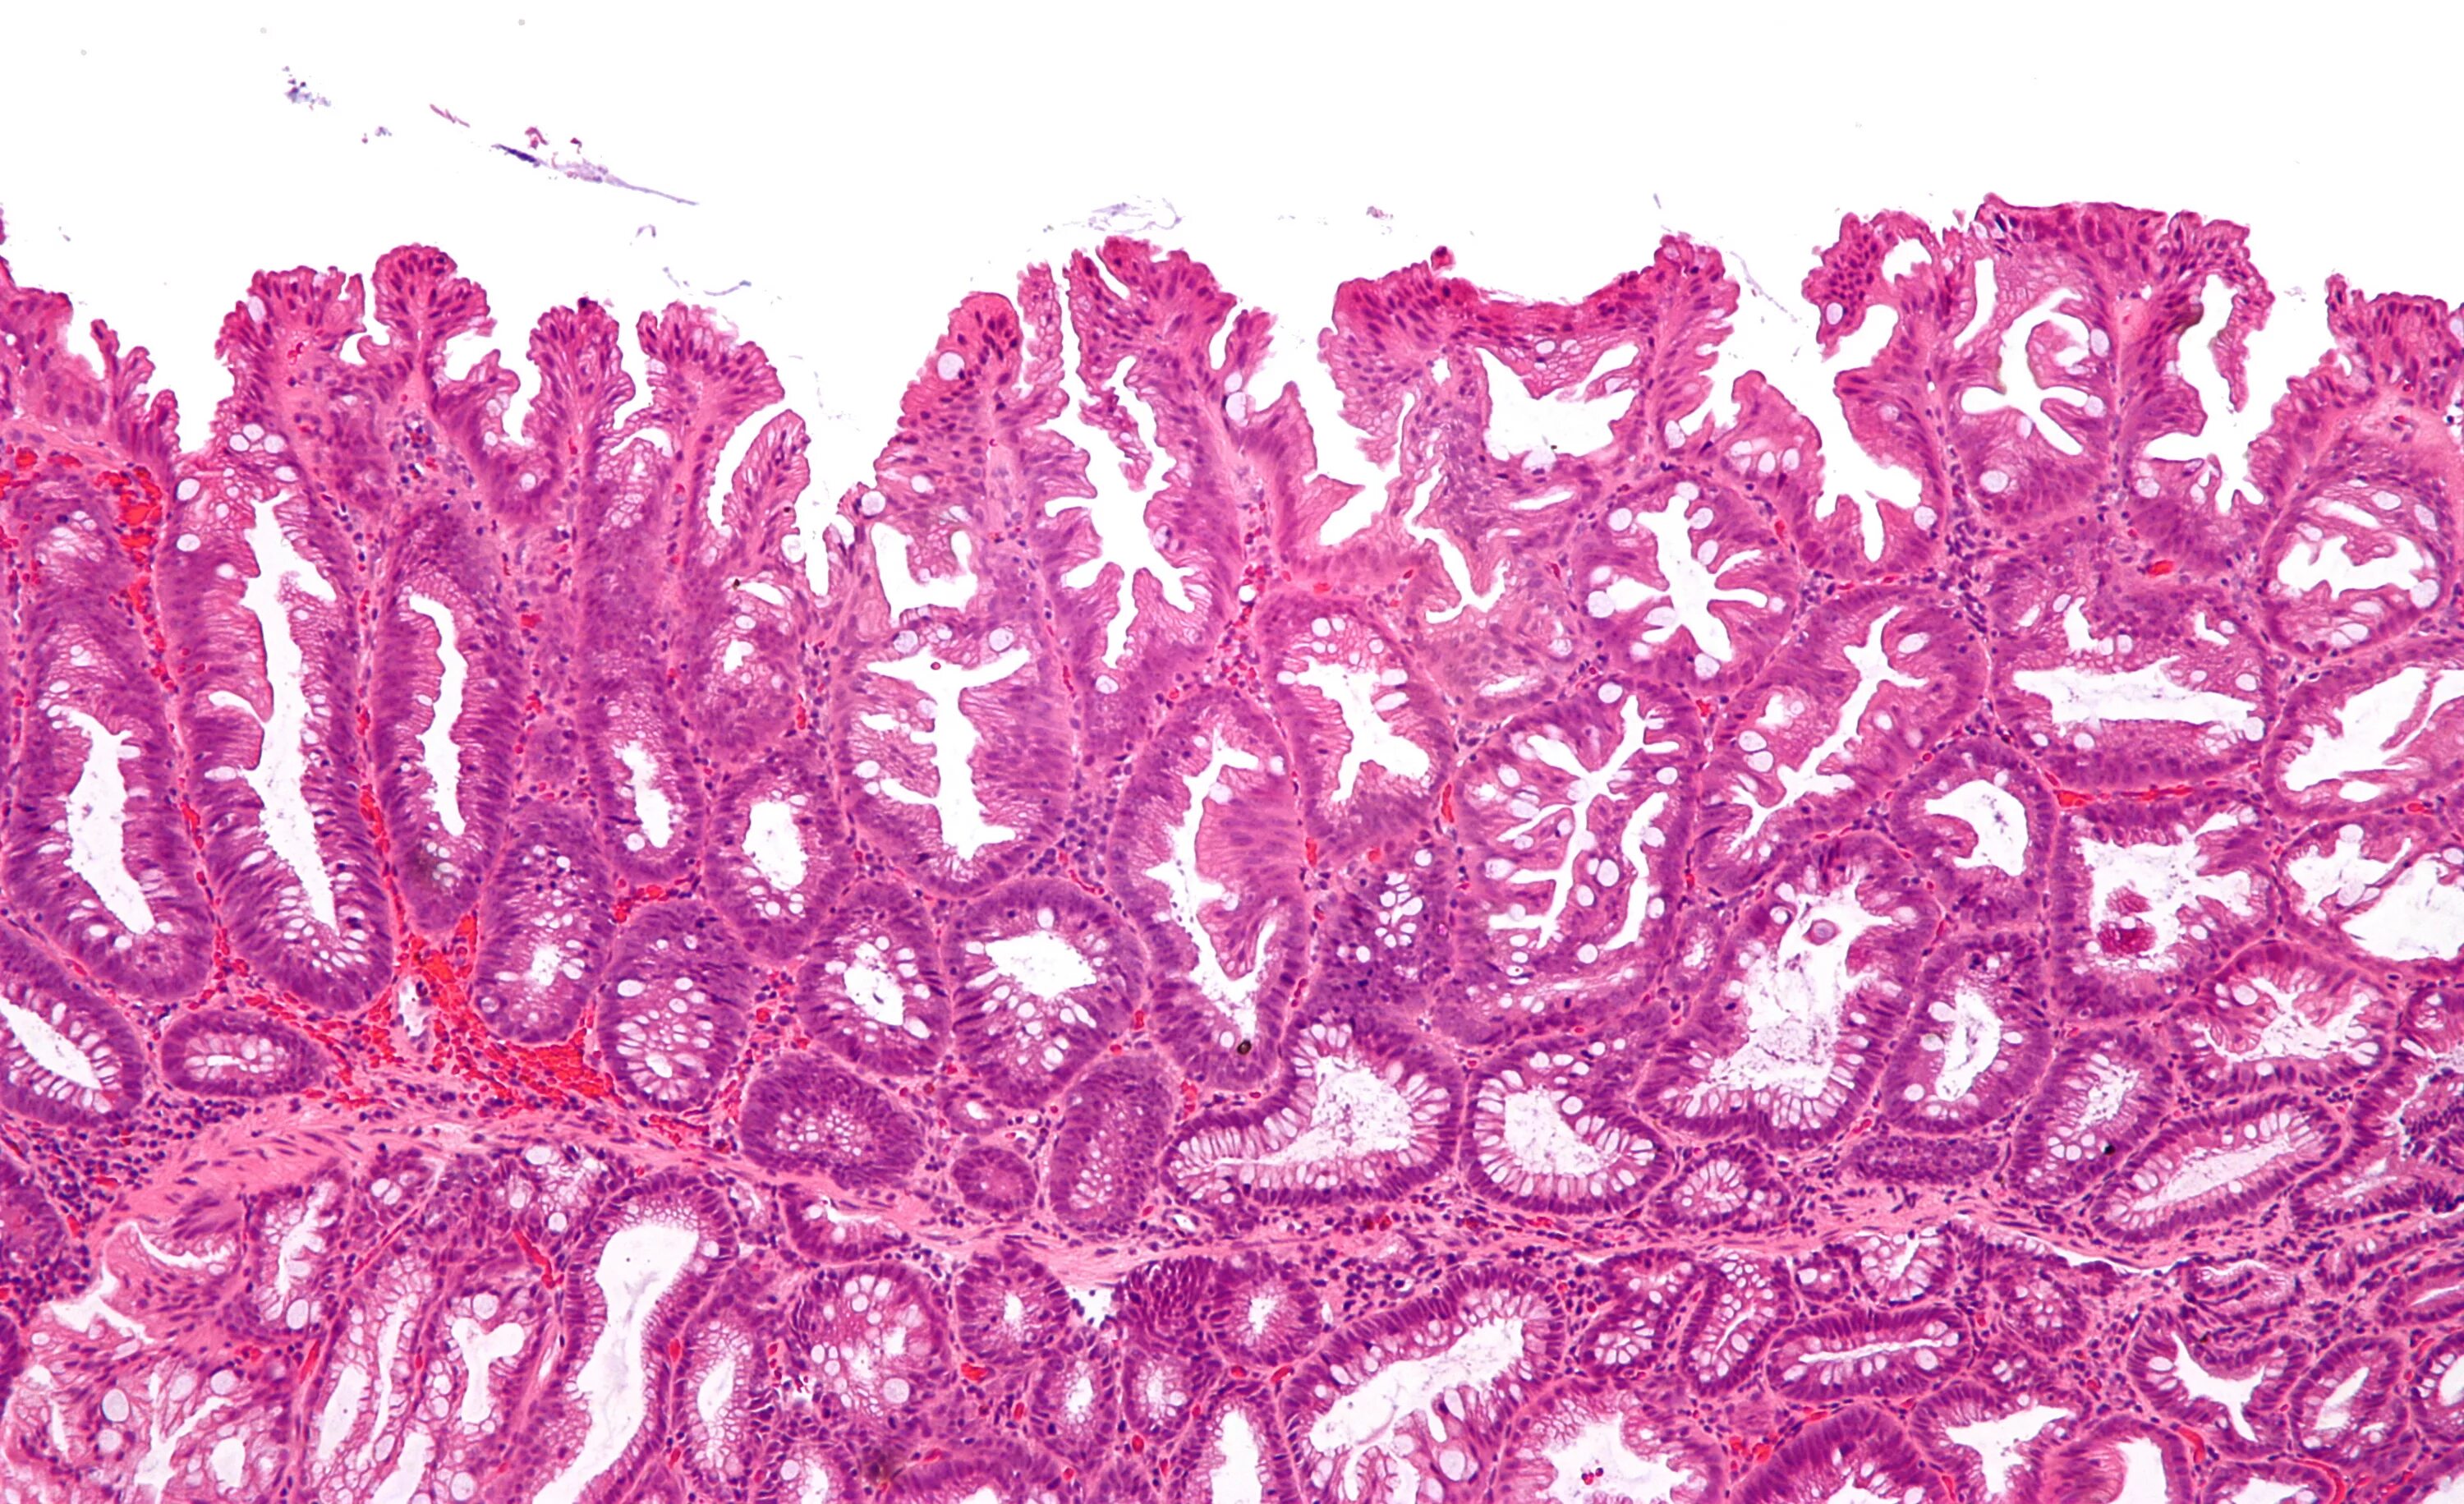

Полипы толстой кишки гистология